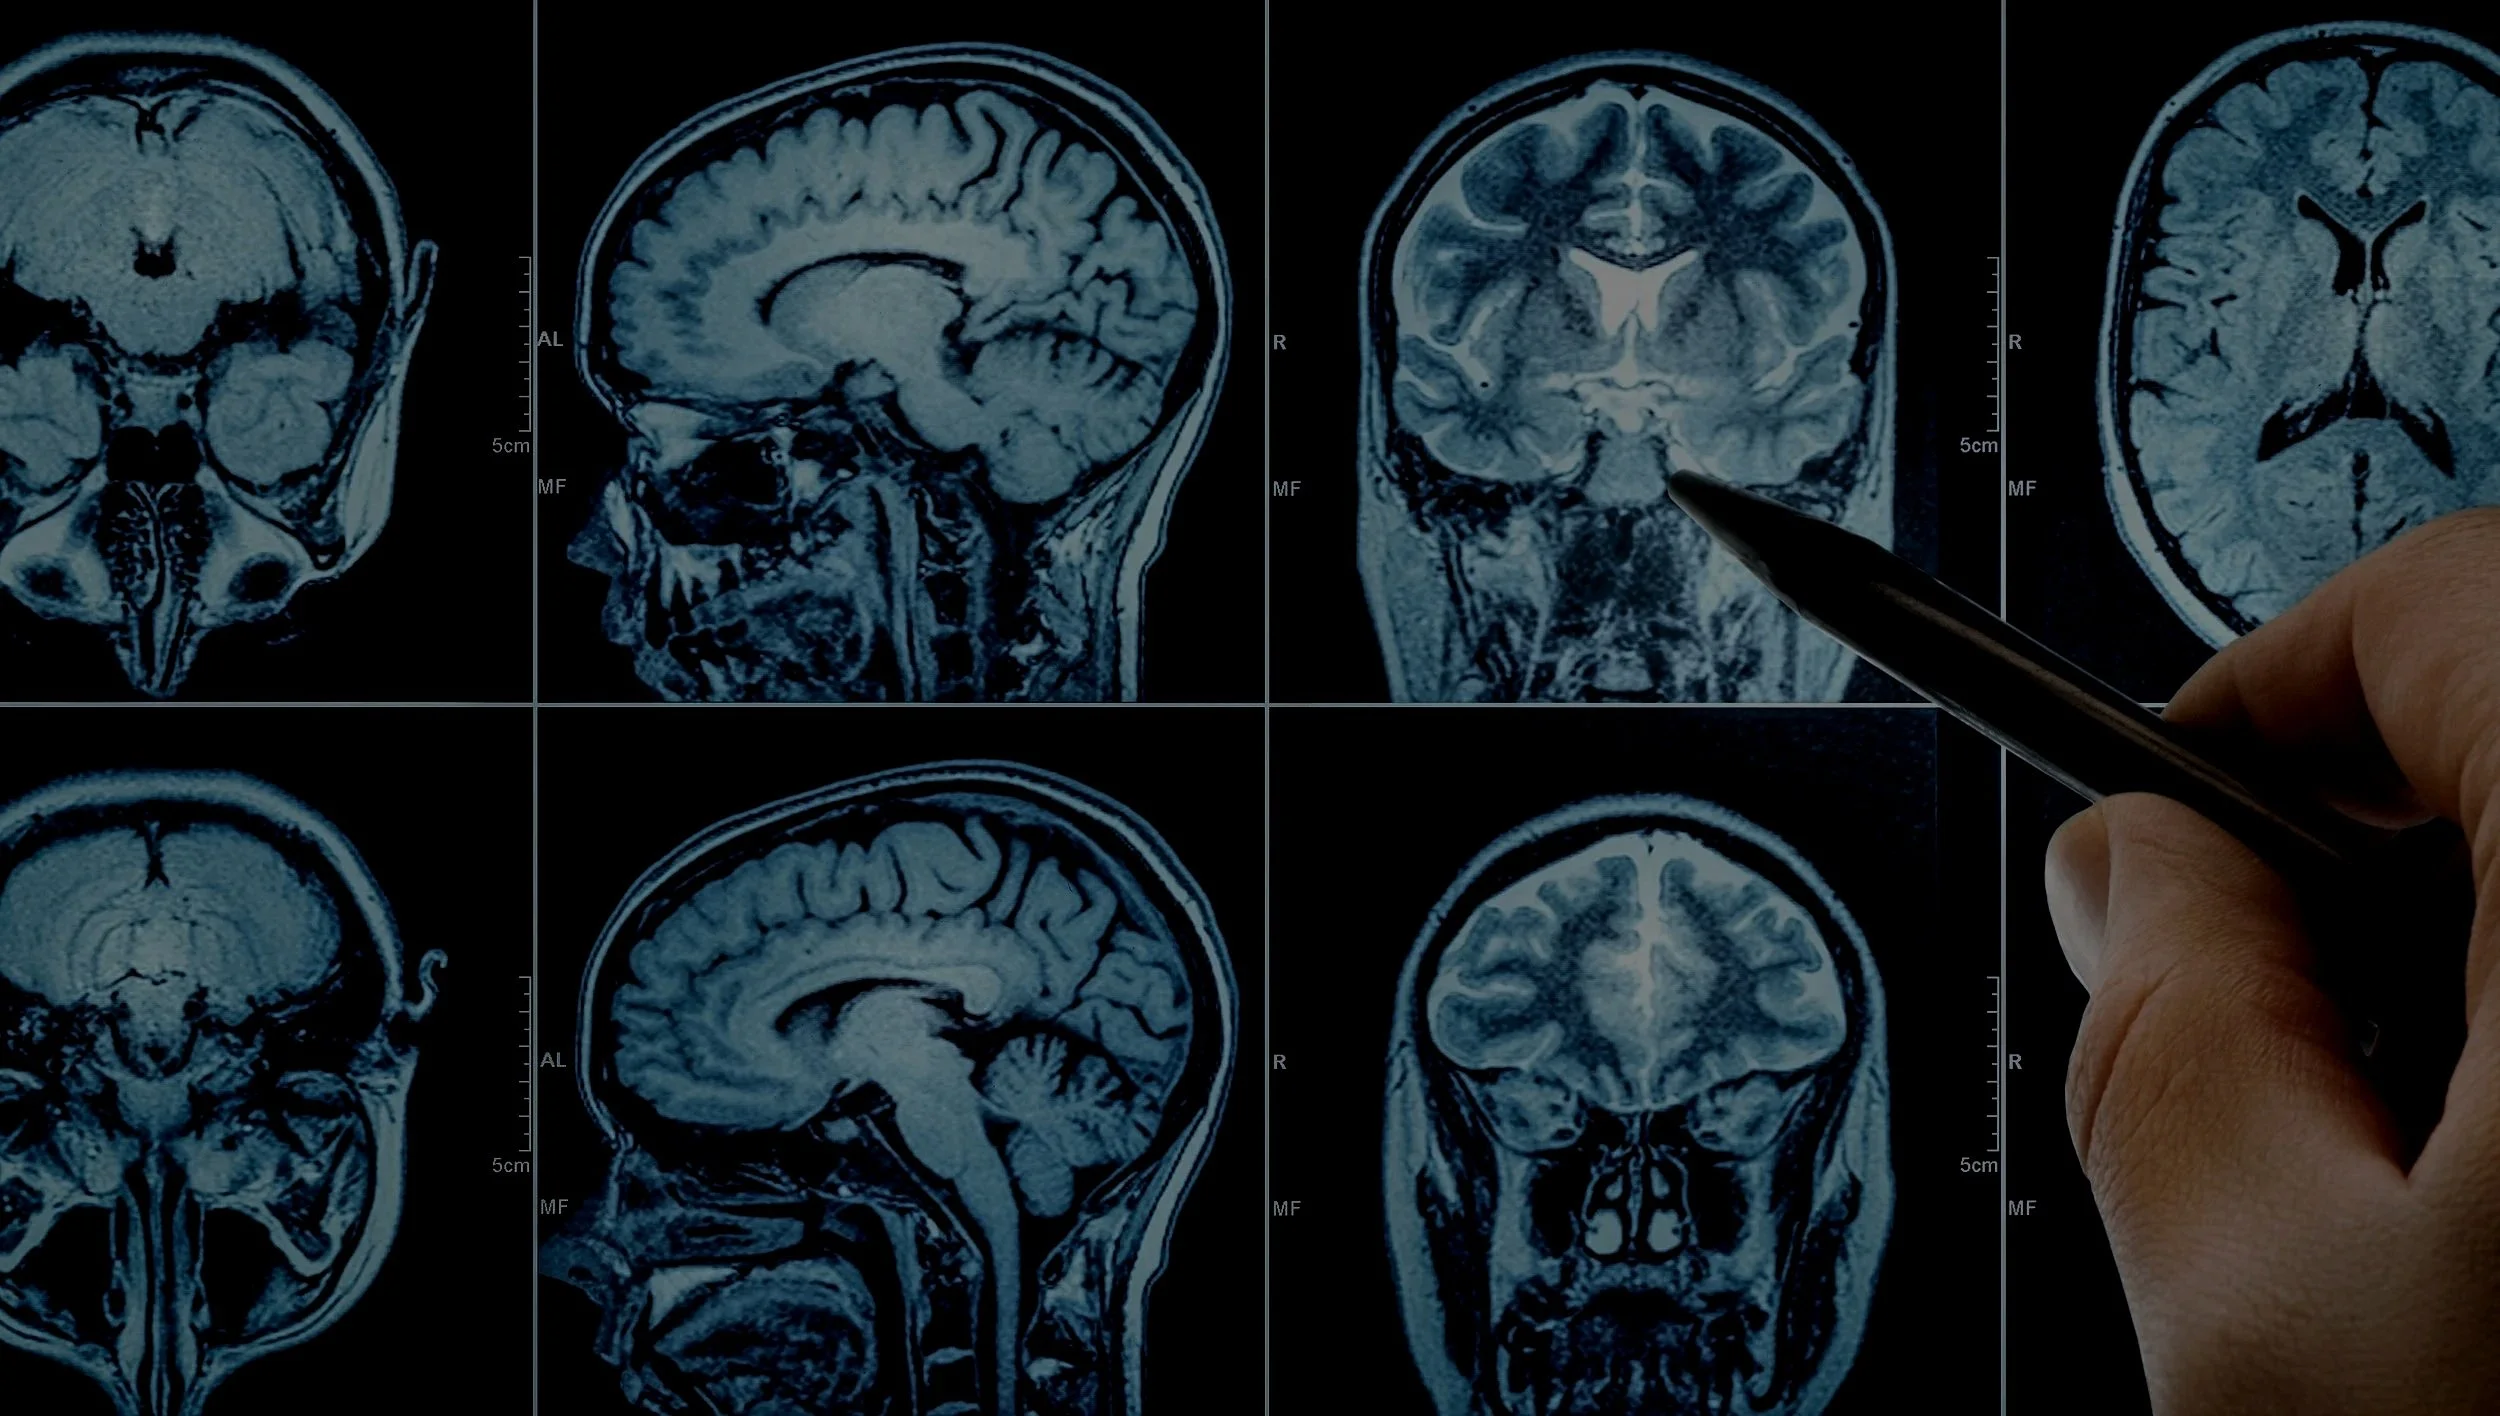

TETRAPHARM is a Danish biopharmaceutical company that specializes in the development of pharmaceutical drugs aimed at the central nervous system and the immune system to treat neurological diseases and mental health disorders.

We advance CNS therapies through neuroscience and drug delivery innovation

At present, we have multiple candidates intended for obesity (with neurological focus), chronic pain, Alzheimer’s and mental health disorders in our clinical pipeline